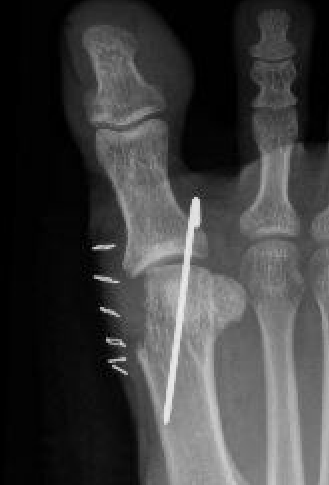

Lapidus Procedure / TMT arthrodesis + DTSP

Indications

- moderate to severe HV

- TMTJ hypermobility

- metatarsus primus varus

Technique

Triplanar correction - coronal / sagittal / rotational